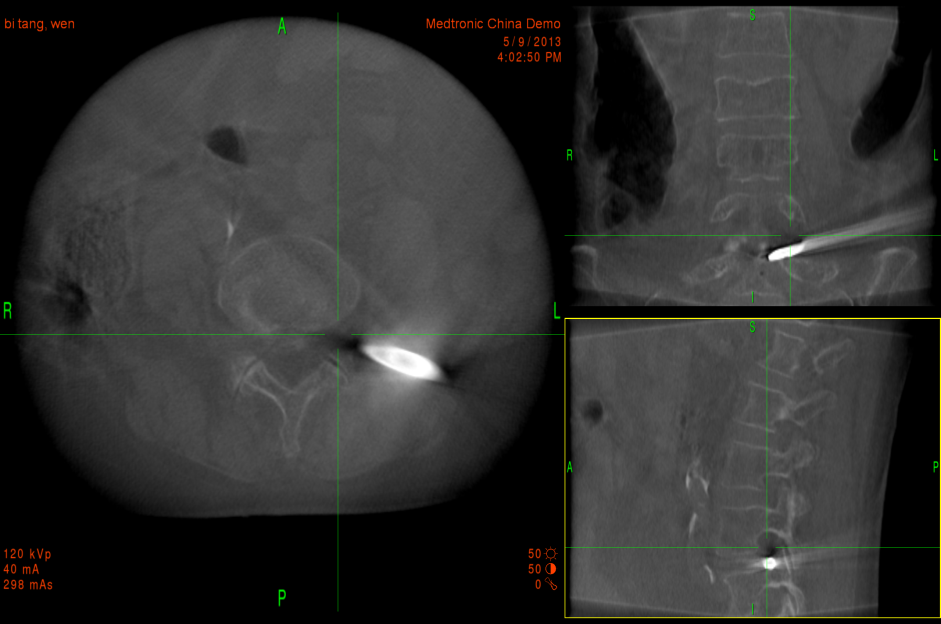

(4)沿导丝逐级扩张软组织,建立工作通道(图8)。

图8 三维下工作通道显示情况

(5)O型臂多维外科成像系统证实通道建立良好(图9)。

图9 三维立体成像显示工作通道